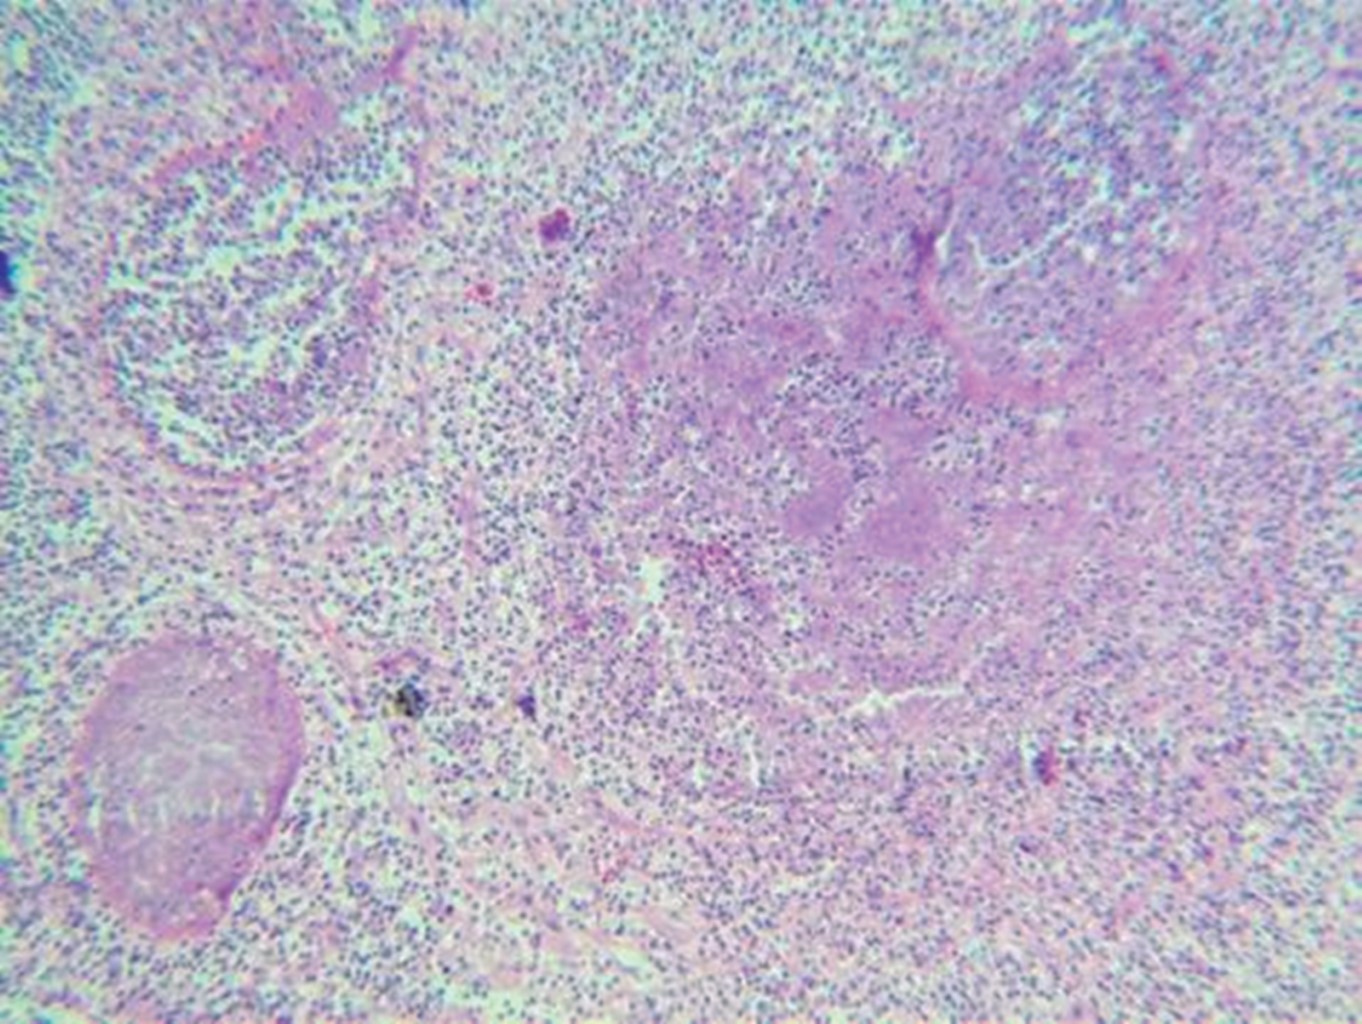

We present the case of 33-year-old male with multiple risky sexual partners. He was treated by a private physician, who performed an ultrasound and clinically corroborated the diagnosis of orchi-epididymitis, for which he received antibiotic treatment with no improvement. Three weeks later he sought a second opinion; a new ultrasonography scan was performed, and the diagnosis of orchi-epididymitis was confirmed, so he was treated again with antibiotics without remission of symptoms. One month later he experienced left testicular enlargement (approximately 10 × 8 cm), weight loss, asthenia and adynamic, so while seeking a third opinion, he went to a public hospital where he underwent a left orchiectomy on suspicion of seminoma, being discharged after 48 hours. That same day he presented constant pain, inability to pass gases and to evacuate, progressive abdominal distention, nausea and vomiting of gastro-alimentary content, so he requested a fourth opinion and underwent a laparoscopy procedure for intestinal occlusion. Multiple implants were found throughout the small intestine as well as retroperitoneal lymph node growth that caused intestinal occlusion at the level of the Treitz angle. A derivative gastrostomy and jejunostomy for feeding were performed, and lymph node biopsies were taken. His evolution was torpid, and he died on the third postoperative day. Two days after his death, a histopathological report of both surgeries was received, which concluded testicular tuberculosis (Figures 1 and 2) and a report of the ELISA test for HIV was received, which was positive.

Figure 2